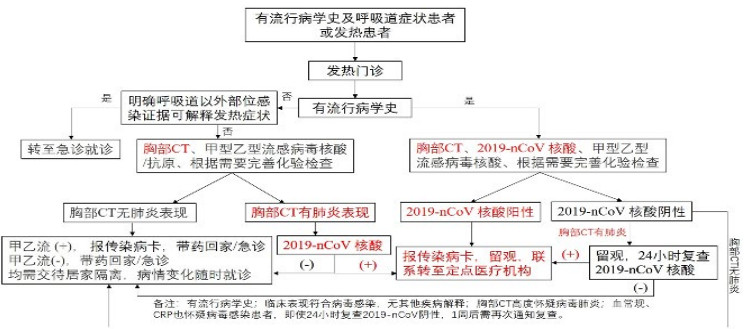

在本研究中,胸部CT正常的患者,无论是否有流行病学史及发热、呼吸道症状等,新型冠状病毒核酸检测均为阴性,故胸部CT可能作为新型冠状病毒感染筛查的一项快速而敏感的手段。基于以上研究结果,笔者在急诊发热门诊推荐以下流程用于筛查新型冠状病毒感染患者(图 2)。需特别注意,除所有发热患者外,有流行病学史和呼吸系统症状的患者(定义同上)均需到发热门诊进行筛查。另外,若患者有流行病学史、临床表现符合病毒感染而无其他疾病解释、胸部CT高度怀疑病毒性肺炎、血常规、CRP亦怀疑病毒感染,即使24 h复查新型冠状病毒核酸阴性,1周后也需再次通知复查。

| 图 2 急诊发热门诊新型冠状病毒感染筛查流程 Fig 2 Screening process for novel coronavirus infection in fever clinic |

综上所述,新型冠状病毒感染患者无特异性临床症状,但胸部CT阴性对新型冠状病毒感染具有很高的阴性预测价值。基于以上发现,笔者推荐急诊与发热门诊采取以上基于流行病学史、胸部CT阳性再进行新型冠状病毒核酸检测的筛查流程以降低漏诊率并提高筛查效率。